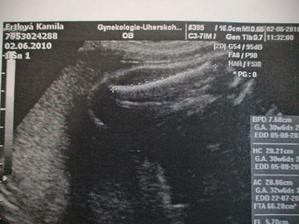

22.7. KO v rizikovce... ozvy, utz, tlak